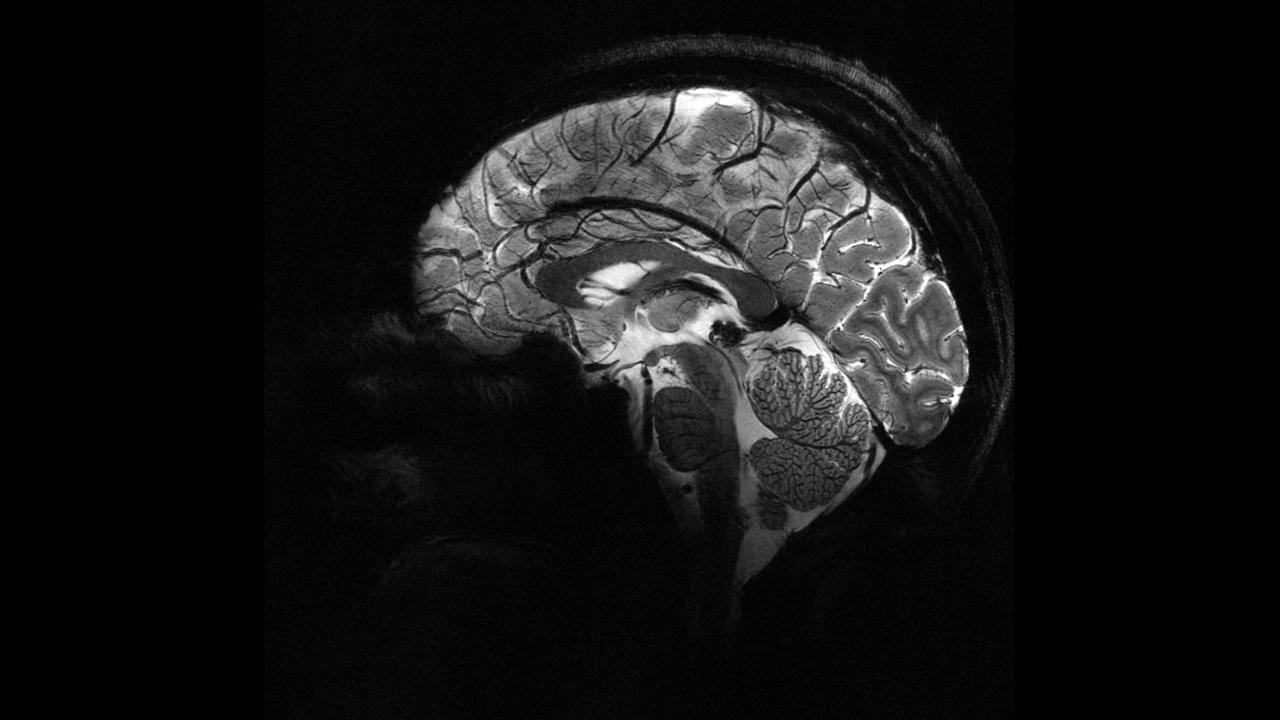

Epilepsiye farklı nedenler yol açsa da, vakaların yaklaşık yüzde 30’u beyindeki yapısal anormalliklerden kaynaklanıyor. Ancak bu lezyonlar, özellikle de beynin kıvrımlarının derinliklerinde saklı olan en küçük olanlar, çoğu zaman MR görüntülerinde fark edilmiyor.

Melbourne Kraliyet Çocuk Hastanesi’nden pediatrik nörolog Emma Macdonald-Laurs liderliğindeki ekip, çocuk beyin görüntüleri üzerinde yapay zekâ modeli eğiterek yaban mersini büyüklüğünde ya da daha küçük lezyonları ortaya çıkarmayı başardı.

Araştırmada kortikal displazi ve fokal epilepsi hastaları üzerinde testler yapıldı. Daha önce MR sonuçları “normal” raporlanan bu çocukların yüzde 80’inde aslında gizli lezyonlar olduğu belirlendi.

Yapay zekâ aracı hem MR hem de PET taramalarını analiz ettiğinde, bir test grubunda yüzde 94, diğerinde yüzde 91 başarı oranı yakaladı. İlk gruptaki 17 çocuktan 12’si beyin lezyonlarının çıkarılması için ameliyat edildi ve 11’i artık nöbetsiz yaşıyor.